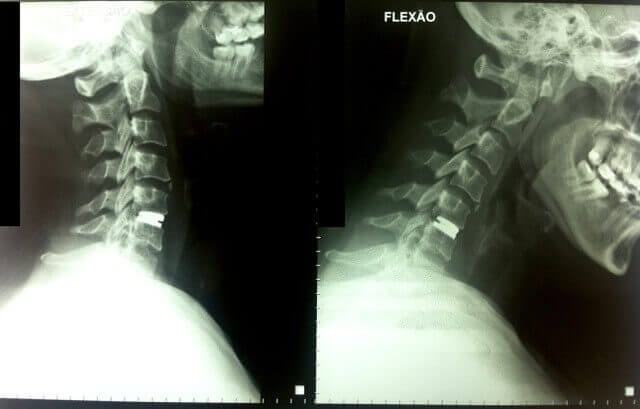

Hoje em dia oferecemos a possibilidade da Artroplastia Cervical. Esta técnica mais moderna, consiste em remover o disco cervical doente e substituí-lo por um disco artificial que imita as propriedades de sustentação e movimentos de um disco cervical sadio. Estudos que acompanharam as pessoas submetidas à Artroplastia Cervical por mais de 10 anos, mostraram uma superioridade desta técnica em comparação com a técnica da artrodese (fixação) nos quesitos de controle de dor, necessidade de re-operação e necessidade de operação dos discos vizinhos ao que foi operado inicialmente.